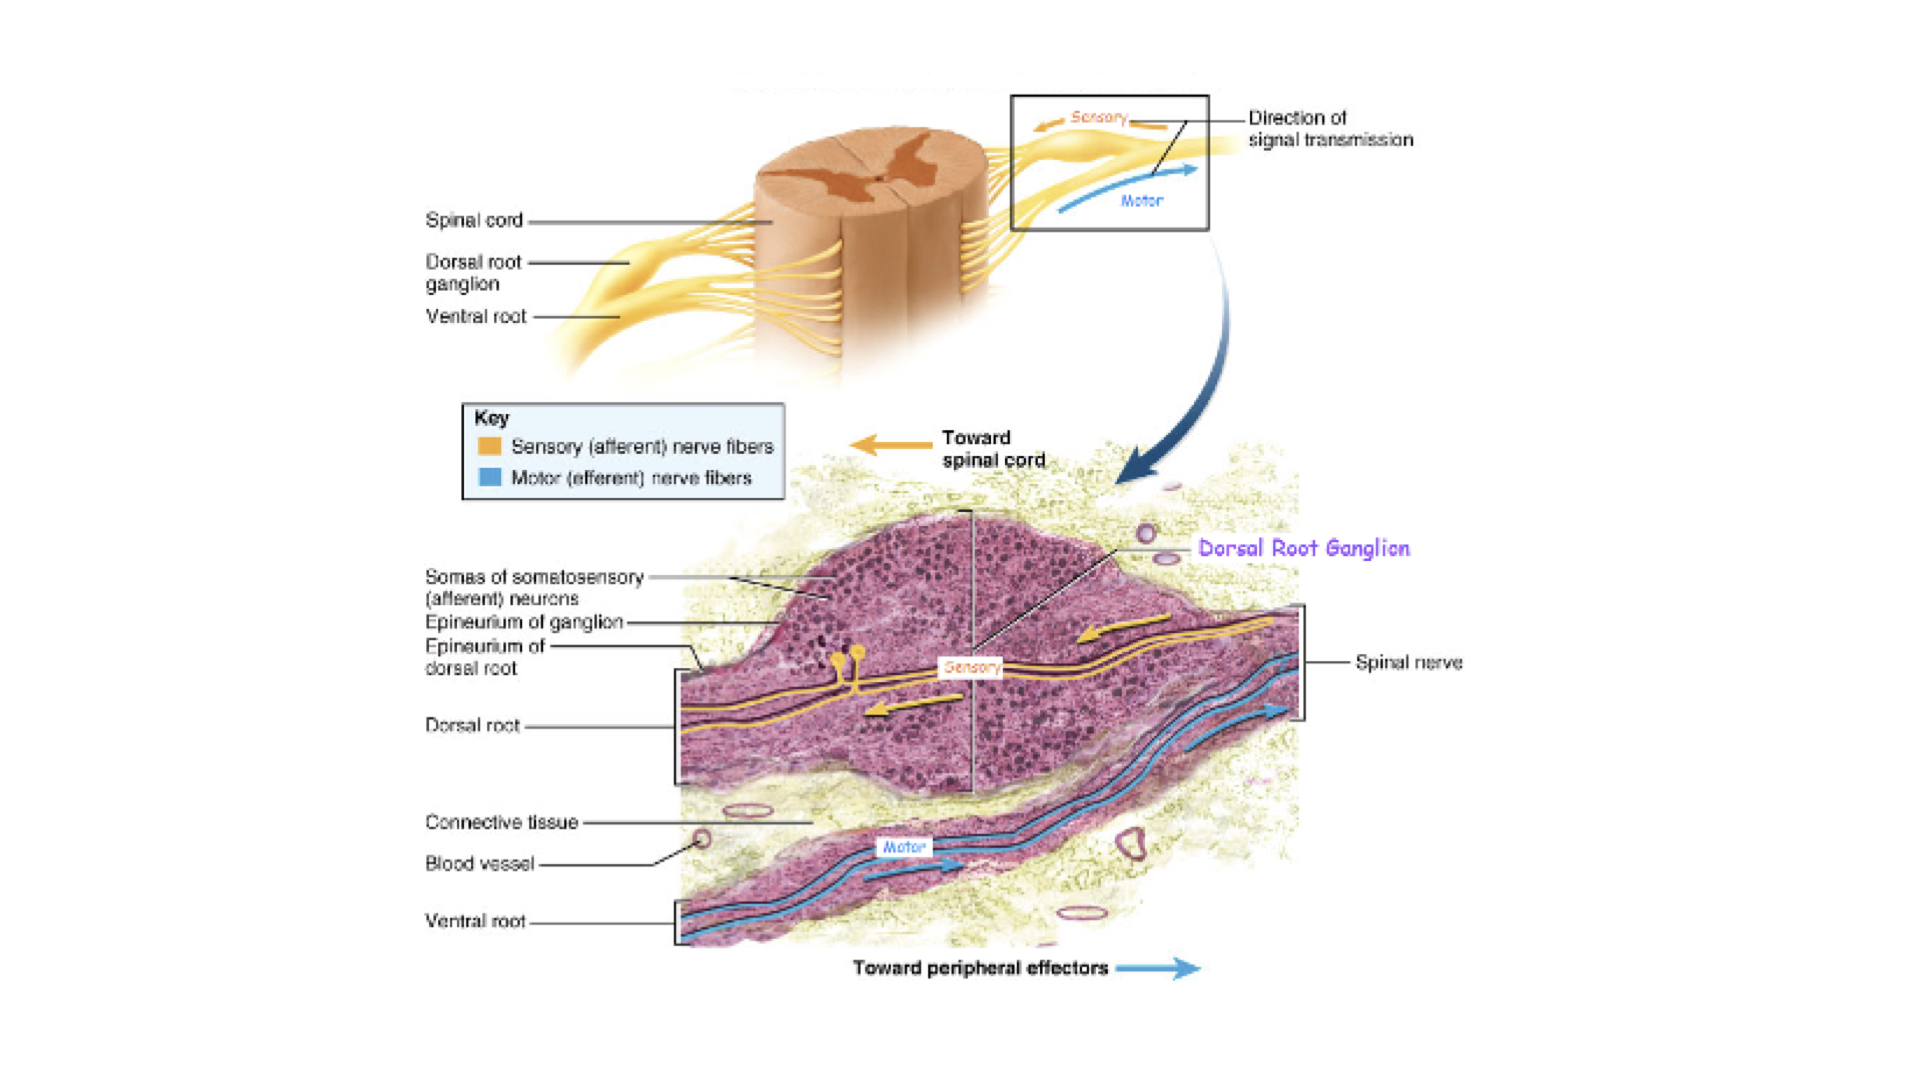

6. dorsal roots – sensory, afferent fibers, dorsal root ganglion, structurally unipolar, neurons from the periphery

7. ventral roots- motor, efferent fibers, dendrites and cell bodies in ventral horns, structurally - multipolar

1. There are 31 pairs of spinals--one pair between each pair of vertebrae. these nerves are directed to specific areas of the body. Nerves are bundles of neurons just like muscles are buddies of muscle fibers. Spinals contain both sensory and motor neurons, Sensory neurons enter the spinal on the dorsal side--dorsal root. Most sensory neurons are unipolar and the cell bodies for each sensory neuron are found in a ganglion along the dorsal root.

Motor neurons have their cell bodies in the gray natter of the spinal cord and exit on the ventral side--ventral root. Just outside of the spinal cord, the spinal nerve is made up of both types of neurons.

The nerve bundle has layers of connective tissue just like muscles did. The difference is that with nerves we use the prefix neuro-- instead of myo-.